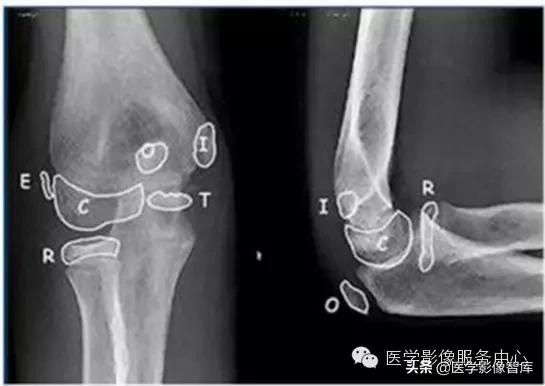

肘关节的X线解剖肘关节常规X线片包括伸肘前后位及屈肘90°的侧位(图1)。正位像肱桡关节间隙清晰,呈下凹的浅弧形;肱尺关节间隙有尺骨滑车切迹重叠而变暗,呈上凹的弧形,故而正位片上肘关节间隙呈波浪状。屈肘侧位片,肱尺关节间隙清晰,呈半环形,前为冠突,后为鹰嘴。肱桡关节掌侧清晰,背侧部分和尺骨冠突相重叠。此时通过桡骨纵轴线的延长线也穿过肱骨小头中心。

伸肘正位片上,肱骨、尺骨长轴线形成向外165°~170°的夹角,此为生理性前臂外翻角,男性一般大于女性。若小于l65°叫肘外翻,大于190°叫肘内翻,如果是180°则叫直肘(图1-1),均属异常表现。肱骨长轴与尺骨长轴在内下方的夹角谓之提携角,正常范围5°~20°之间,女大于男。